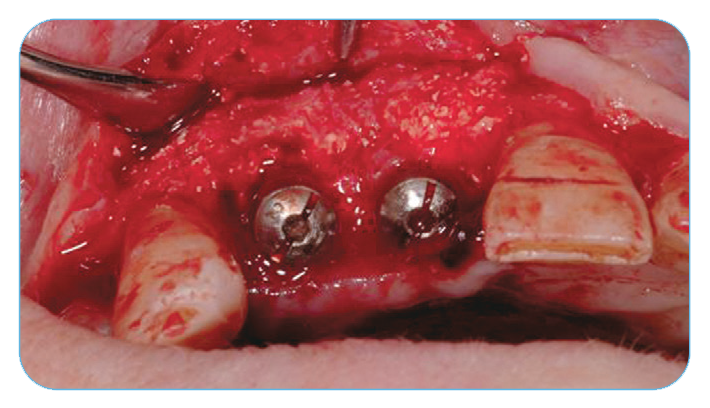

Fig. 1. Extraction sockets of the four maxillary incisors and immediate implant placement.